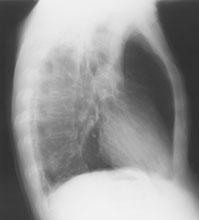

Ein 71-jähriger Italiener beklagt sich über einen reduzierten Allgemeinzustand und subfebrile Temperaturen. Er raucht seit 45 Jahren.

Husten und Auswurf hätte er immer gehabt, berichtet der Patient. Mit der Frage nach einem Infiltrat wird ein Röntgenbild verordnet:

Thorax seitlich

Welche Befunde imponieren (mehrere richtige Antworten möglich)?